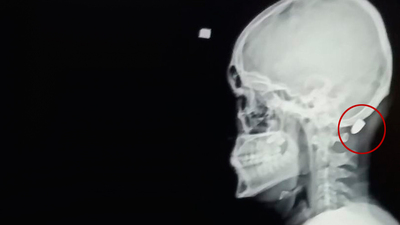

DHA'nın haberine göre, olay, dün saat 14.30 sıralarında Karadağ Yaylası'nda meydana geldi. Ali Kuleyin yaylada gezindiği sırada ensesinde acı hissetti. Genç, ensesini arkadaşlarına gösterdi. Kuleyin'in ensesinde mermi çekirdeği olduğunu fark eden arkadaşları, durumu sağlık ekiplerine haber verdi. Gelen sağlık ekiplerince ilk müdahalesi yapılan Kuleyin, ambulansla Vakfıkebir Devlet Hastanesi'ne kaldırıldı. Mermi, ameliyatla çıkarıldı. Sağlık durumunun iyi olduğu bildirirken Ali Kuleyin, tedavisinin ardından taburcu edildi.